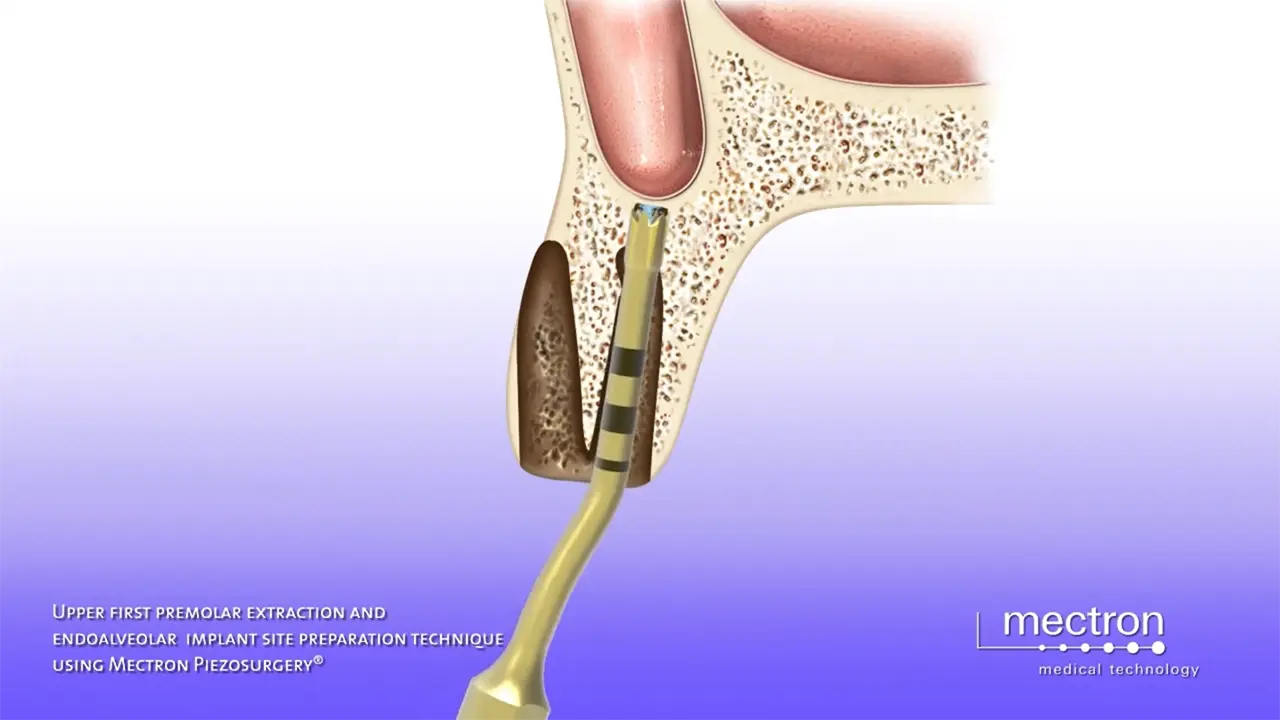

Extraction and ultrasonic preparation of the implant site

Prof. Tomaso Vercellotti